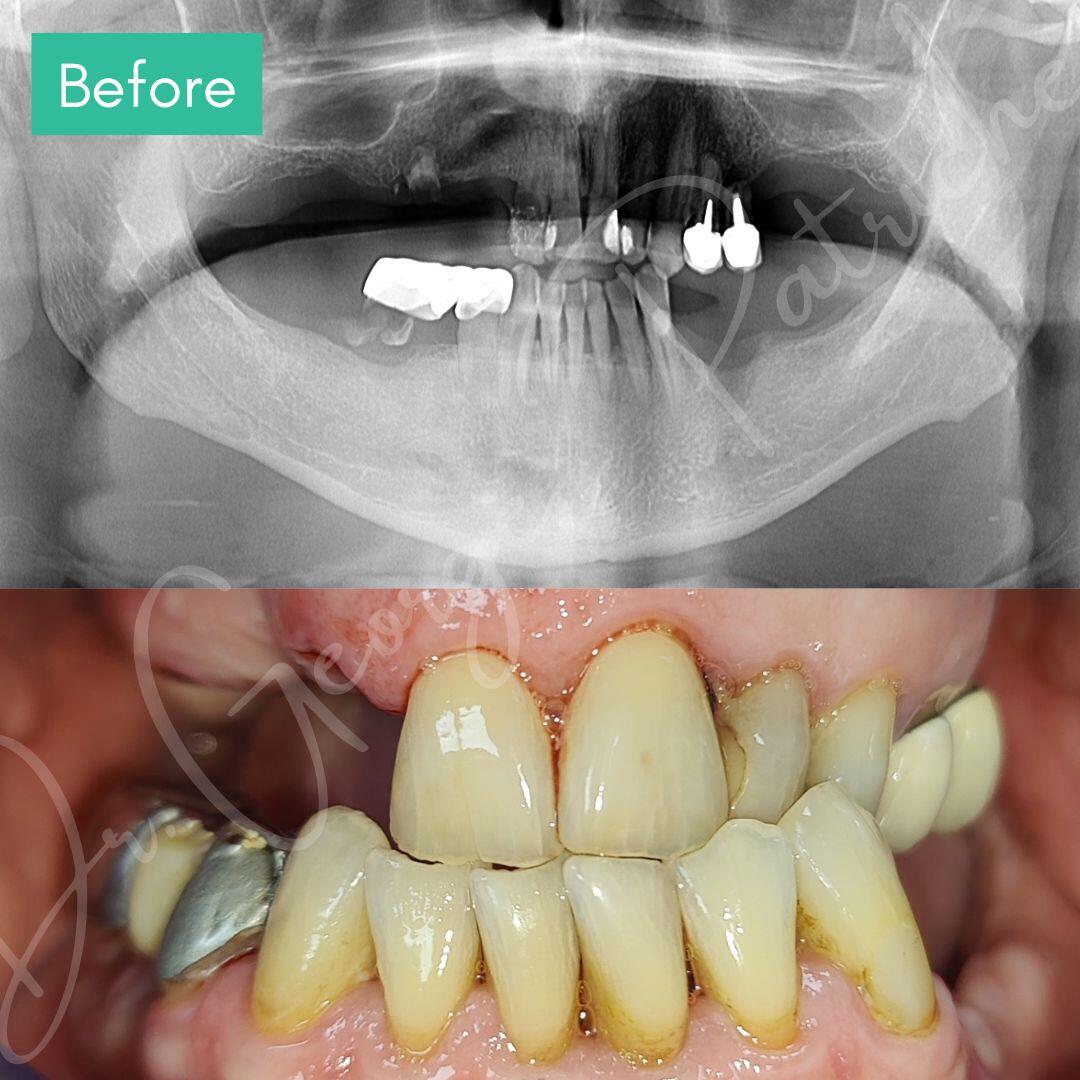

Before & After